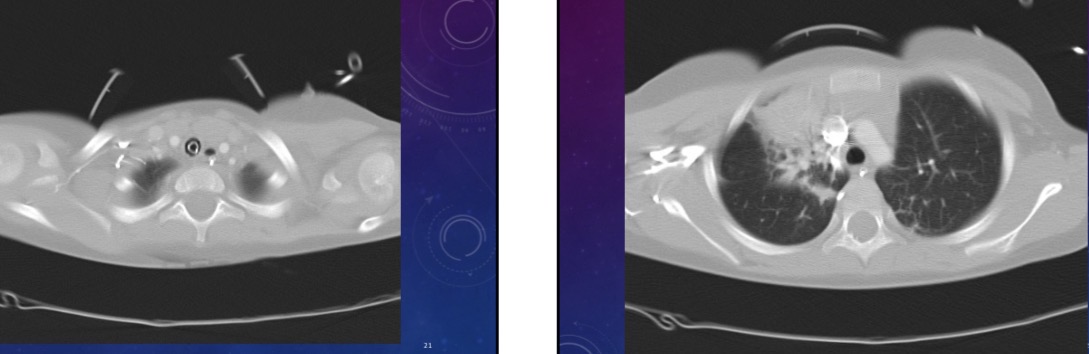

What does chest scan show

Left pneumothorax, atelectasis in right upper and left lower lobes